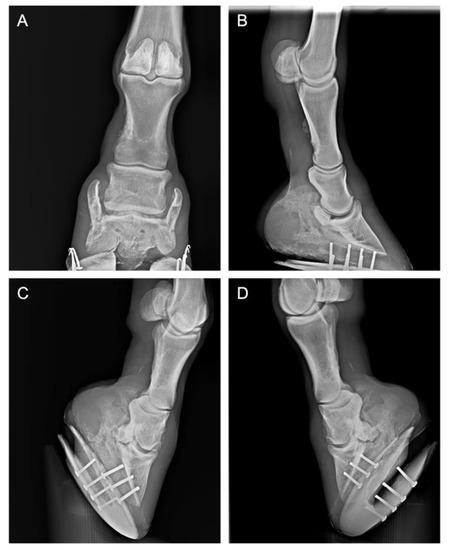

| (3) 14-year-old Holst. mare jumping horse | Distal intertarsal joint arthritis | Lameness Flexion test | 2 3 | 1 2 | 0 1 | 0 0 | 0 0 |

| (4) 15-year-old NRPS mare jumping horse | Distal intertarsal joint arthritis | Lameness Flexion test | 3 3 | 2 2 | 1 1 | 0 1 | 0 0 |